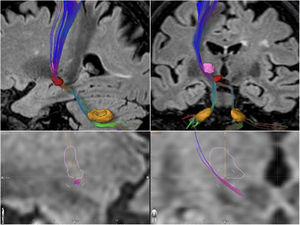

Patients and methodsAll the patients included in the study underwent the same procedure. Segmentation of the Vim nucleus was performed on volumetric MRI sequences using the Brainlab® software (Boston Scientific; Natick, MA, USA). The target was defined as the intersection of 2 planes at the inferior surface of the Vim10: an oblique coronal orientation plane crossing the Vim nucleus at its centre and parallel to its major axis, and a sagittal plane crossing the Vim nucleus at its centre (Fig. 1), contralateral to the affected hemibody. The procedure was performed using a 3T MRI scanner (GE Healthcare Medical Systems and Solutions; Waukesha, WI, USA) and an ExAblate 4000 MRgFUS system (InSightec Inc.; Haifa, Israel). A confirmation sonication was performed to assess the clinical effect and detect any adverse effects (subtherapeutic temperature, ideally between 49 °C and 52 °C). When the clinical effect was considered satisfactory by the assessing neurologist and no adverse events were observed, at least 2 additional therapeutic sonications were delivered at the same anatomical site (55 °C to 60 °C)8; the procedure was monitored clinically and with continuous thermography. The eligibility threshold for HIFU treatment was a skull density ratio (SDR) ≥ 0.35, which was determined in the weeks before treatment. All patients received domperidone at 30 mg/day over the 3 days prior to the procedure, 8 mg ondansetron one hour before the procedure, and an additional 4 mg ondansetron before the start of the sonications.